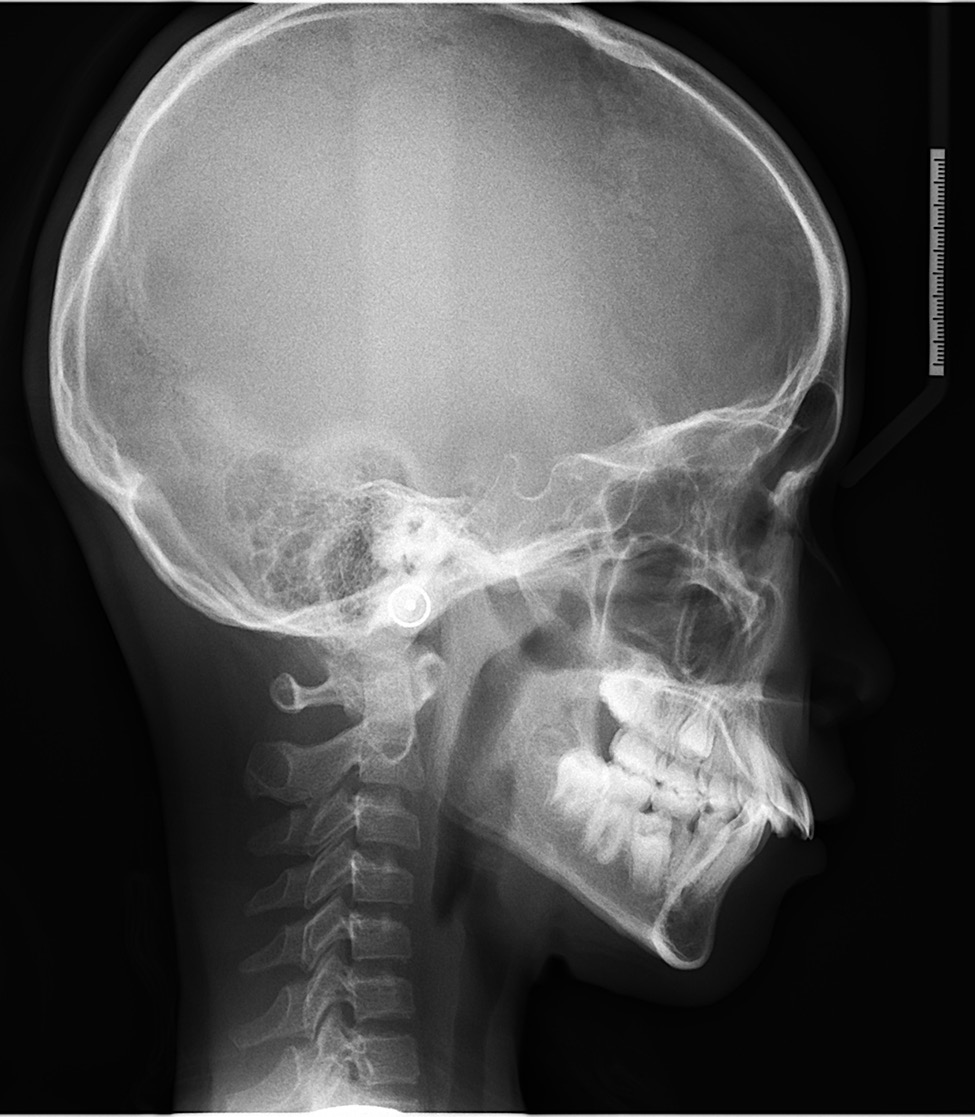

替牙期是孩子上下颌骨和牙齿生长发育的快速期,也是早期矫治的关键时期。大家要知道孩子在10岁左右上颌骨发育已经完成85%,因此重点要放到下颌骨。

在孩子8-10岁(上下4颗门牙换完)之间,如果能充分利用孩子下颌骨生长的潜能进行矫正,不但能矫正牙齿问题,同时对矫正孩子的面型起到一定作用,比如骨性嘴凸、下颌后缩等,还可以引导恒牙的正常萌出和排齐。

3、恒牙早期(女孩10—13岁、男孩12—14岁)孩子们进入青春期,同时也迎来了生长发育的高峰期,也是牙齿矫正的“终极黄金期”。

这个时期孩子恒牙已经基本萌出完毕,牙齿的排列和咬合关系也基本稳定。

如果错过上述年龄段,这一时期发现孩子存在较严重的错颌畸形,可以在这个时期进行综合性的牙齿矫正治疗,另外还有一定机会利用后部生长发育空间,降低孩子拔正畸牙的几率。